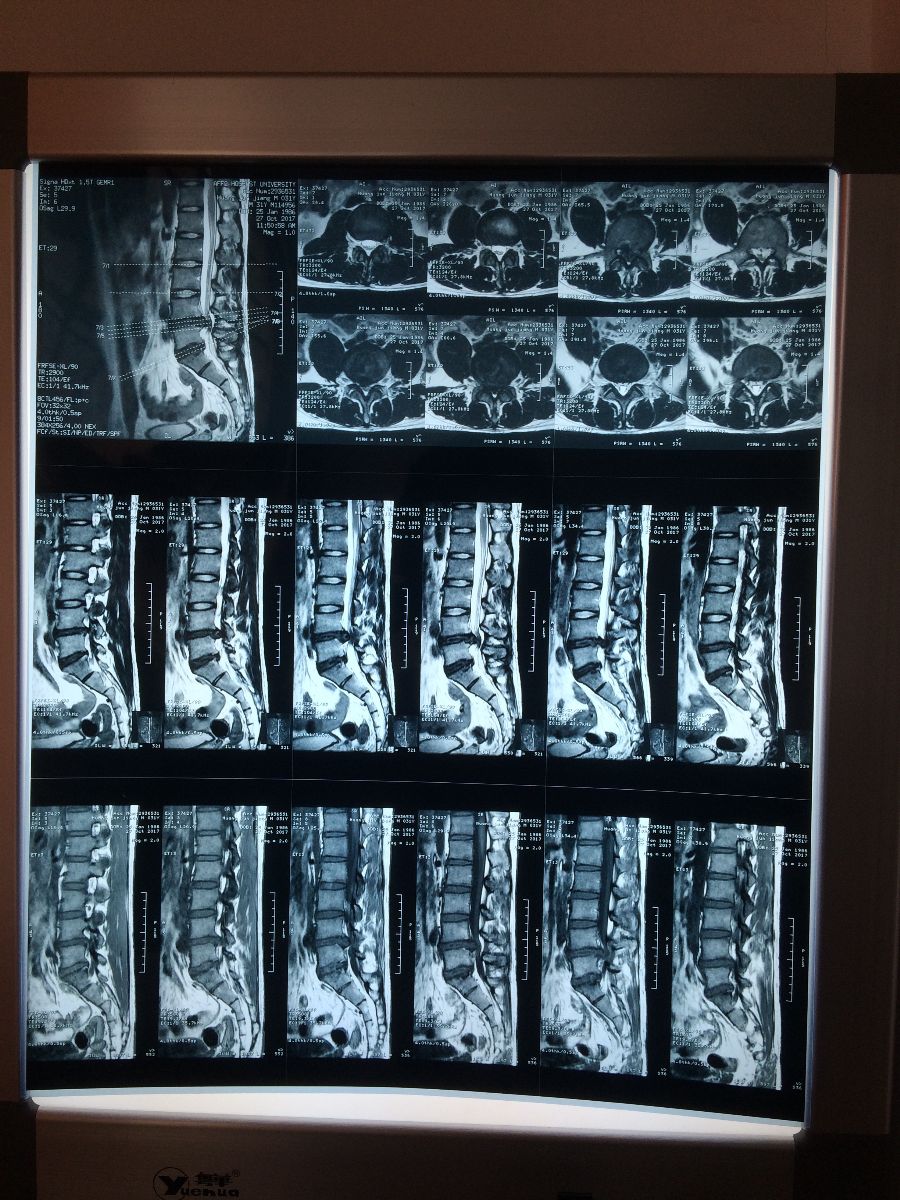

腰椎盘突出(伴椎管狭窄)

姓名:黄xx 性别:男 年龄:31

主诉:腰痛伴双臀部及双下肢放射痛1年余。

病史:1年前因搬重物后出现腰部酸痛,伴双侧臀部放射痛,在当地医院就诊,症状未见明显好转,近2个月病情加重并伴有双下肢放射痛,跛行,查MRI示:1.L4/L5椎间盘变性并突出(中央型),伴椎管狭窄;2.L5S1椎间盘变性并膨出;3.腰椎曲度变直,L4、5椎体轻度骨质增生。经朋友介绍于2017年11月22号至本中心就诊。

MRI示:

1.L4/L5椎间盘变性并突出(中央型),伴椎管狭窄;

2.L5S1椎间盘变性并膨出;

3.腰椎曲度变直,L4、5椎体轻度骨质增生。